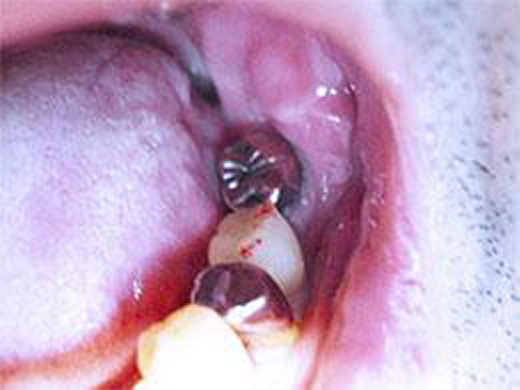

5. インプラントと骨が結合する期間

一次手術が終わったあと、インプラントが顎の骨としっかり結合するまで待機期間を設けます。

期間は個人差がありますが、一般的には3〜6ヶ月程度が目安です。

その間、必要に応じて仮歯を使用していただき、見た目や噛み合わせに大きな支障が出ないよう配慮します。

6. 上部構造(被せ物)の装着

インプラントと骨の結合が確認できたら、上部構造と呼ばれる被せ物を装着していきます。